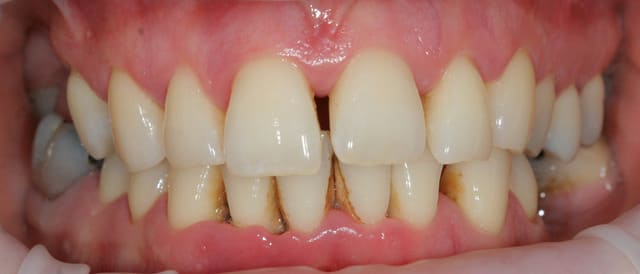

Paro ultra agressive chez une jeune femme de 30 ans.

Dans toute cette période, je n'ai pour ainsi dire quasiment jamais eu de cas de parodontite agressive aussi importante que celle ci.

la patiente est très jolie, elle a 30 ans, a consulté deux ou trois dentiste en l'espace de 10 ans, le dernier détartrage date il y a trois ans et il n'a pas été terminée apparemment car la patiente avait trop de douleurs, et aujourd'hui elle est adressée par un hôpital parisien qui devait lui poser des implants et qui devant la panoramique a renoncé sans pour autant la diriger correctement.

Une contention sera réalisée en bas (mobilités très importantes) . En haut curieusement il n'y a que très peu de mobilités.

...il y a autre chose: trés peu de dents postérieures soutiennent l'occlusion, et on est en début d'effondrement, avec les antérieures qui commencent à partir en éventail.

on est clairement devant une parodontite agressive généralisée avec comme facteur de risque le Tabac et un facteur aggravant l'occlusion ...